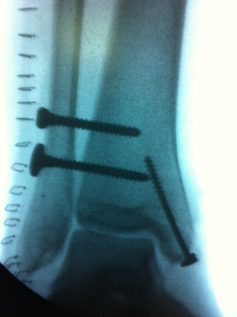

Lesiones, bien agudas o crónicas, que afectan a los huesos, articulaciones, ligamentos o músculos, y cuyo tratamiento definitivo, generalmente, es quirúrgico.